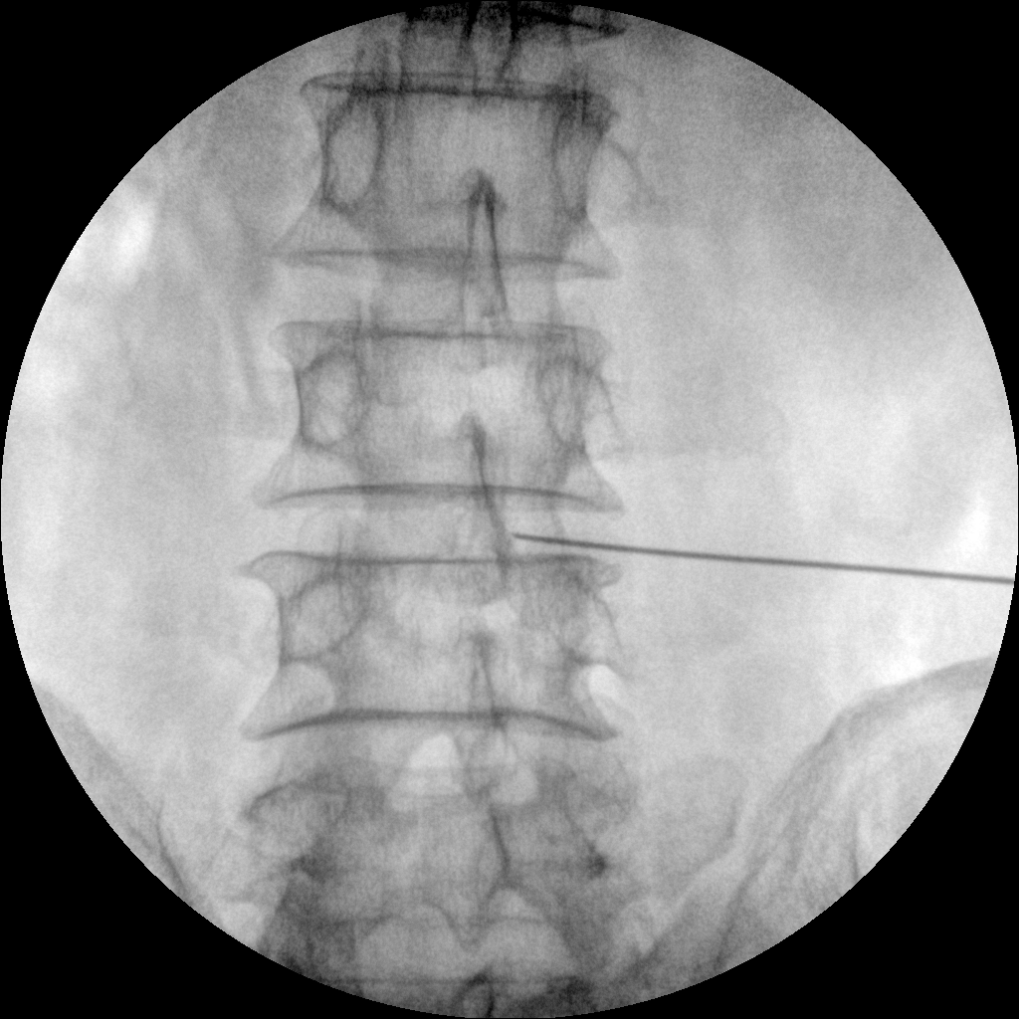

PLX112C 系列高频移动式手术X射线机

手术导航定位系统